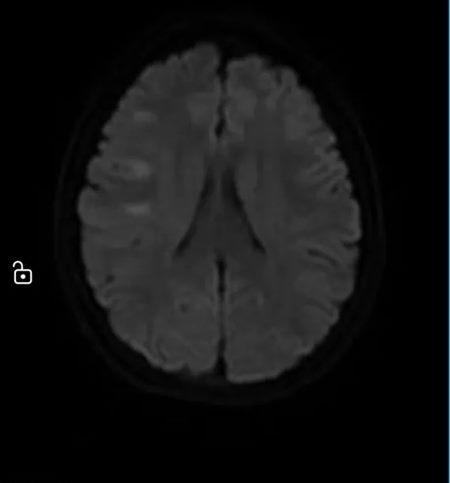

清晨,急诊科送来一名12岁的女孩。突发偏瘫、不能说话——确诊为“急性脑梗死”。

神经内科评估、神经外科接力、影像瞬间出片……

最终决定:脑血管造影 + 经皮颅内动脉取栓术。

手术台上,团队从她堵塞的颈内动脉中,取出一条近10厘米长的血栓。